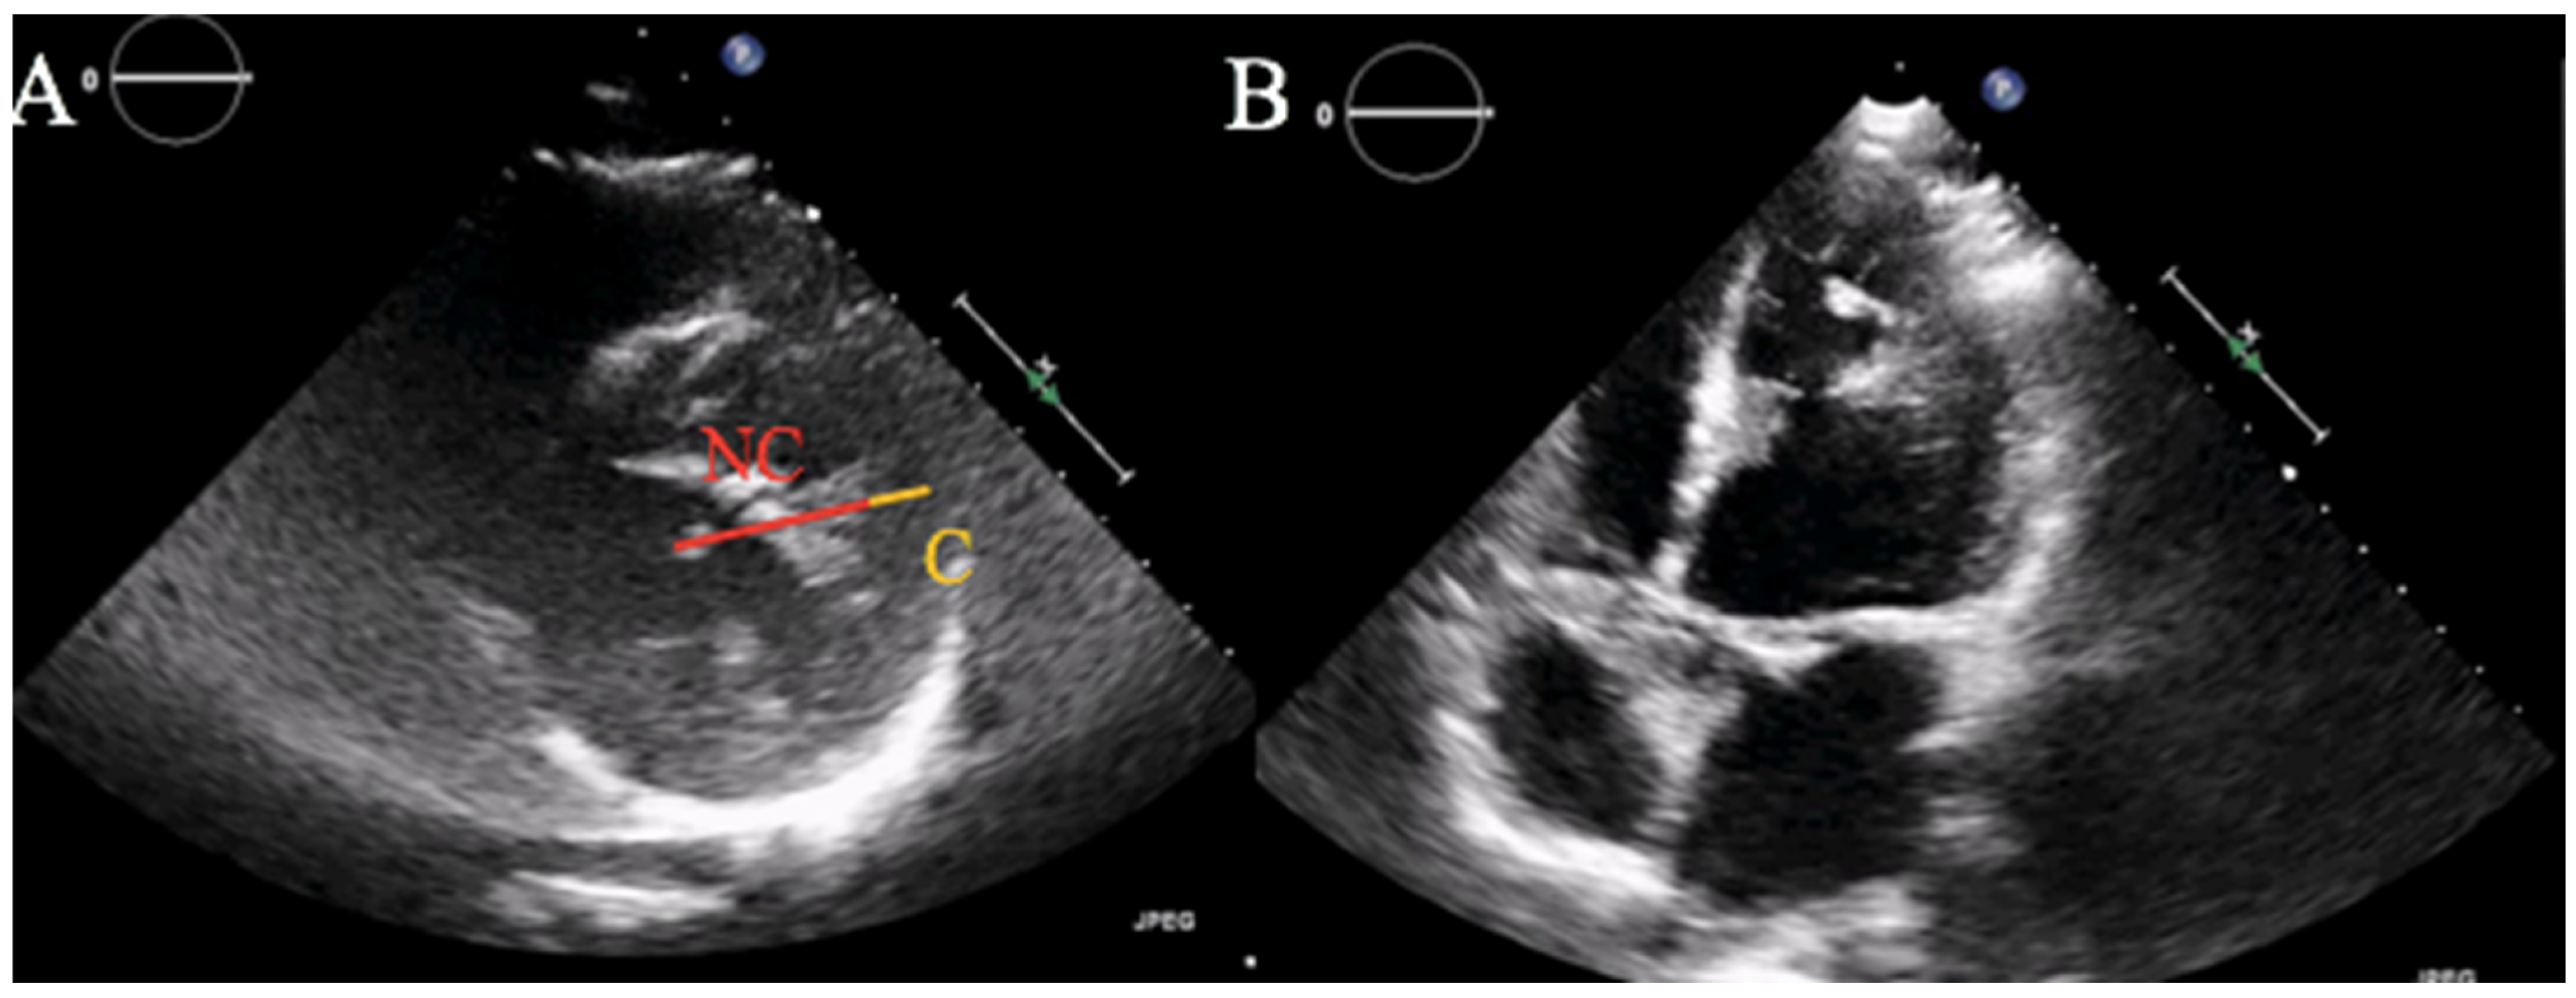

The patient was transferred to the Cardiac Intensive Care Unit. Blood tests showed low-density lipoprotein (LDL) cholesterol of 137 mg/dL and normal glycosylated hemoglobin. Transthoracic echocardiogram (TTE) documented moderate left ventricular (LV) dilatation, severe LV dysfunction (ejection fraction 30%) with apical, septal and anterior wall akinesis, and lateral wall hypertrabecularization with multiple prominent trabeculations and deep intertrabecular recesses communicating with the ventricular cavity, with an end systolic NC/C ratio > 2 in parasternal short axis view, suggestive for LVNC (Figure 2A,B).

Figure 2.

Transthoracic echocardiogram. (A) Parasternal short axis view showing an end systolic NC/C ratio > 2, diagnostic for LVNC according to Jenni’s criteria. (B) Apical four chambers view with evidence of hypertrabecular appearance of the left ventricle at the apex and lateral wall.